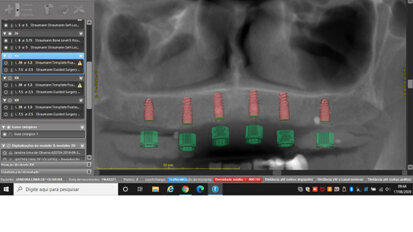

Rehabilitace Straumann